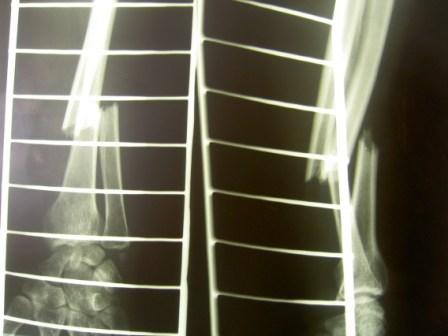

В анамнезе была попытка работать со сканером, не очень удобно, и для получения хорошего качества изображения необходим сканер хорошей разрешающей способности. и самое главное наилучшие результаты достигаются с применением сканеров проходящего света, а не отражающие (много помех), т.к. снимки тоже зачастую имеют артефакты и низкое качество. Последние 3 года испльзуем негатоскоп и цифровой аппарат Lumix Panasonik 7,0 мегапикселей. Снимаем в режиме макросъёмки без вспышки

Из всего прежнего многообразия самым практичным оказался этот способ.